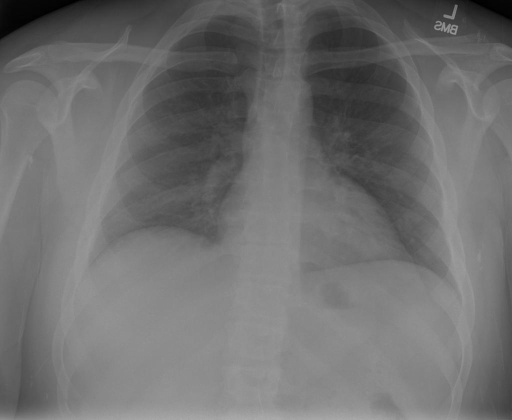

# 本文贡献  - 借助ChatGPT以及公开的数据集,我们构造了一个`X光影像-诊断报告`对的医学多模态数据集; # 数据集 - [MIMIC-CXR](https://physionet.org/content/mimic-cxr-jpg/2.0.0/)是一个公开可用的胸部X光片数据集,包括377,110张图像和227,827个相关报告。 - [OpenI](https://openi.nlm.nih.gov/faq#collection)是一个来自印第安纳大学医院的胸部X光片数据集,包括6,459张图像和3,955个报告。 在上述工作中,报告信息都为非结构化的,不利于科学研究。为了生成合理的医学报告,我们对两个数据集进行了预处理,并最终得到了可以用于训练的**英文报告**。除此之外,为了更好的支持中文社区发展,借助ChatGPT的能力,我们将英文报告进行了中文翻译,并最终形成了可用于训练的数据集。 |数据集|数量|下载链接| |:-|:-|:-| |MIMIC-CXR-zh|-|-| |OpenI-zh|6,423|[诊疗报告](./data/Xray/openi-zh.json) 、[X光影像](https://pan.baidu.com/s/13GBsDMKf6xBZBSHpoWH_EA?pwd=k9sh)| # 快速上手 1. 安装环境 ```bash # 安装依赖 pip install -r requirements.txt # 国内换源安装依赖 pip install -i https://mirrors.aliyun.com/pypi/simple/ -r requirements.txt ``` 此时默认会安装`deepspeed`库(支持`sat`库训练),此库对于模型推理并非必要,同时部分`Windows`环境安装此库时会遇到问题。 如果想绕过`deepspeed`安装,我们可以将命令改为: ```bash # 安装依赖 pip install -i https://mirrors.aliyun.com/pypi/simple/ -r requirements_wo_ds.txt # 安装SwissArmyTransformer pip install -i https://mirrors.aliyun.com/pypi/simple/ --no-deps "SwissArmyTransformer>=0.3.6" ``` 2. 模型推理 CLI推理: ```python python cli_demo.py --from_pretrained checkpoints/finetune-XrayGLM-05-25-01-04 --prompt_zh '详细描述这张胸部X光片的诊断结果' ``` 更多[参数](https://github.com/WangRongsheng/XrayGLM/blob/main/cli_demo.py#L16) # 效果展示 诊断: |X光影像|诊疗报告(医生)|XrayGLM| |:-|:-|:-| ||根据X射线图像,心脏大小正常,肺部看起来很清晰。已经排除了肺炎、积液、水肿、气胸、腺病、结节或肿块的存在。该发现表明一切正常。换句话说,总体印象是胸部正常。|X光片显示,心脏大小正常。肺部没有气胸或胸腔积液的证据。骨骼结构看起来没有任何异常。总的来说,X光片表明没有发现急性心肺疾病的迹象。| ||X光图片显示没有扭曲的区域、可疑的骨质不透明度或胸腺积液。心脏大小轻微增大,但非常稳定。此外,没有气胸的证据,肺野也正常。总体来说,X光片显示没有急性心脏异常,但要注意轻微的心脏扩大。|X光片显示,心脏大小正常。肺部和纵隔轮廓清晰,没有气胸或胸腔积液的证据。骨骼结构完整,没有任何急性异常。| ||心影形态在正常范围内。没有急性骨质异常。有可能出现没有明显的吸水或肺实质状况的线索。没有大面积积液或气胸。有可能怀疑其有误吸或肺实质问题。为了确诊和治疗,可能需要进行适当的影像学随访。|心脏大小正常,肺部和纵隔轮廓清晰。没有急性异常或活动受限的证据。没有任何明显的气胸、胸腔积液或肺不张的迹象。此外,也没有发现任何局灶性骨质异常或其他急性疾病。| 多轮对话: |X光影像|诊疗报告(医生)| |:-|:-| ||右侧主动脉突出观察到。心脏大小正常。胸部未发现明显的肺气肿、胸膜积液或可疑的肺部病变。报告指出已知右侧主动脉情况正常。| ```bash >> X光影像路径:./data/Xray/861_1.png >> 用户:这是一张什么图? >> XrayGLM:这张图片显示的是一张肺部检查的X光片。 >> 用户:请描述这张胸部X光片的诊断结果 >> XrayGLM:心脏大小正常,肺部清晰。没有急性心肺疾病的证据。 >> 用户:是否存在肺气肿? >> XrayGLM:没有肺气肿。心脏大小正常,肺部清晰。没有发现急性心肺疾病的证据。 >> 用户:平时饮食该注意什么? >> XrayGLM:饮食应该健康,均衡。建议增加蛋白质的摄入量,因为蛋白质有助于维持肌肉和骨骼的健康。多食用蔬菜、水果、全谷物以及健康的脂肪来源如橄榄油、鱼类等可以帮助获得足够的维生素和矿物质。此外,避免过度饮酒或吸烟,这些习惯可能会对心脏健康产生负面影响。 ``` # 项目致谢 1. [VisualGLM-6B](https://github.com/THUDM/VisualGLM-6B)为我们提供了基础的代码参考和实现; 2. [MiniGPT-4](https://github.com/Vision-CAIR/MiniGPT-4)为我们这个项目提供了研发思路; 3. ChatGPT生成了高质量的中文版X光检查报告以支持XrayGLM训练; 4. [gpt_academic](https://github.com/binary-husky/gpt_academic)为文档翻译提供了多线程加速; 5. [MedCLIP](https://github.com/RyanWangZf/MedCLIP) 、[BLIP2](https://huggingface.co/docs/transformers/main/model_doc/blip-2) 、[XrayGPT](https://github.com/mbzuai-oryx/XrayGPT) 等工作也有重大的参考意义;  这项工作由[澳门理工大学应用科学学院](https://www.mpu.edu.mo/esca/zh/index.php)硕士生[王荣胜](https://github.com/WangRongsheng) 、[段耀菲](https://github.com/IsBaSO4) 、[李俊蓉](https://github.com/lijunrong0815)完成,同时这项工作受到[檀韬](https://scholar.google.com/citations?hl=zh-CN&user=lLg3WRkAAAAJ)副教授、[彭祥佑](http://www.patrickpang.net/)老师的帮助支持。 *特别鸣谢:[USTC-PhD Yongle Luo](https://github.com/kaixindelele) 提供了有3000美金的OpenAI账号,帮助我们完成大量的X光报告翻译工作 # 免责声明 本项目相关资源仅供学术研究之用,严禁用于商业用途。使用涉及第三方代码的部分时,请严格遵循相应的开源协议。模型生成的内容受模型计算、随机性和量化精度损失等因素影响,本项目无法对其准确性作出保证。即使本项目模型输出符合医学事实,也不能被用作实际医学诊断的依据。对于模型输出的任何内容,本项目不承担任何法律责任,亦不对因使用相关资源和输出结果而可能产生的任何损失承担责任。 # 项目引用 如果你使用了本项目的模型,数据或者代码,请声明引用: ```bash @misc{wang2023XrayGLM, title={XrayGLM: The first Chinese Medical Multimodal Model that Chest Radiographs Summarization}, author={Rongsheng Wang, Yaofei Duan, Junrong Li, Patrick Pang and Tao Tan}, year={2023}, publisher = {GitHub}, journal = {GitHub repository}, howpublished = {\url{https://github.com/WangRongsheng/XrayGLM}}, } ``` # 使用许可 此存储库遵循[CC BY-NC-SA](https://creativecommons.org/licenses/by-nc-sa/4.0/) ,请参阅许可条款。